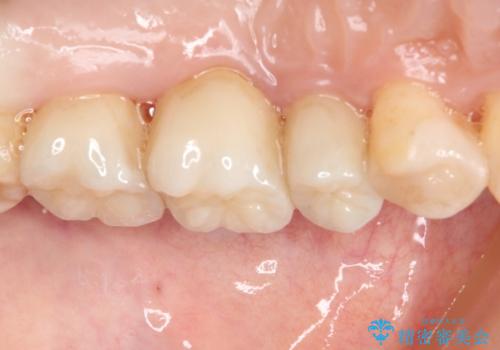

知覚過敏の症状はなくなり、希望通りの白い歯になったと、患者様は大変満足されました。